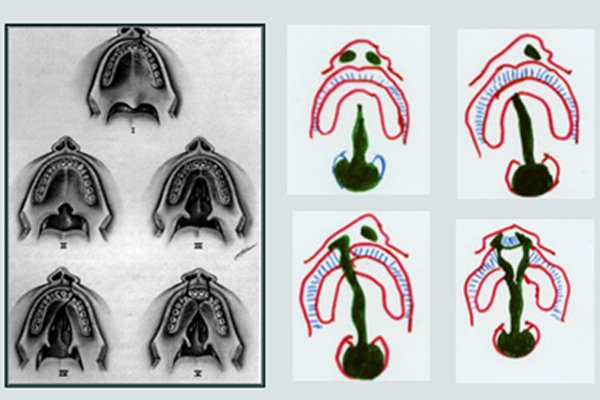

TYPE 1: Defect of red portion of the lip ( Vermilion )

TYPE 2 : Clefts which include vermilion and a portion of the lip musculature Upto the nostril on Affected side but not including the floor of the nostril.

TYPE 3: Unilateral complete clefts involving the full thickness of the lip typically accompanied by a marked deformity of the nose.

TYPE 4: Bilateral clefts of the lip either partial, complete or in combination.